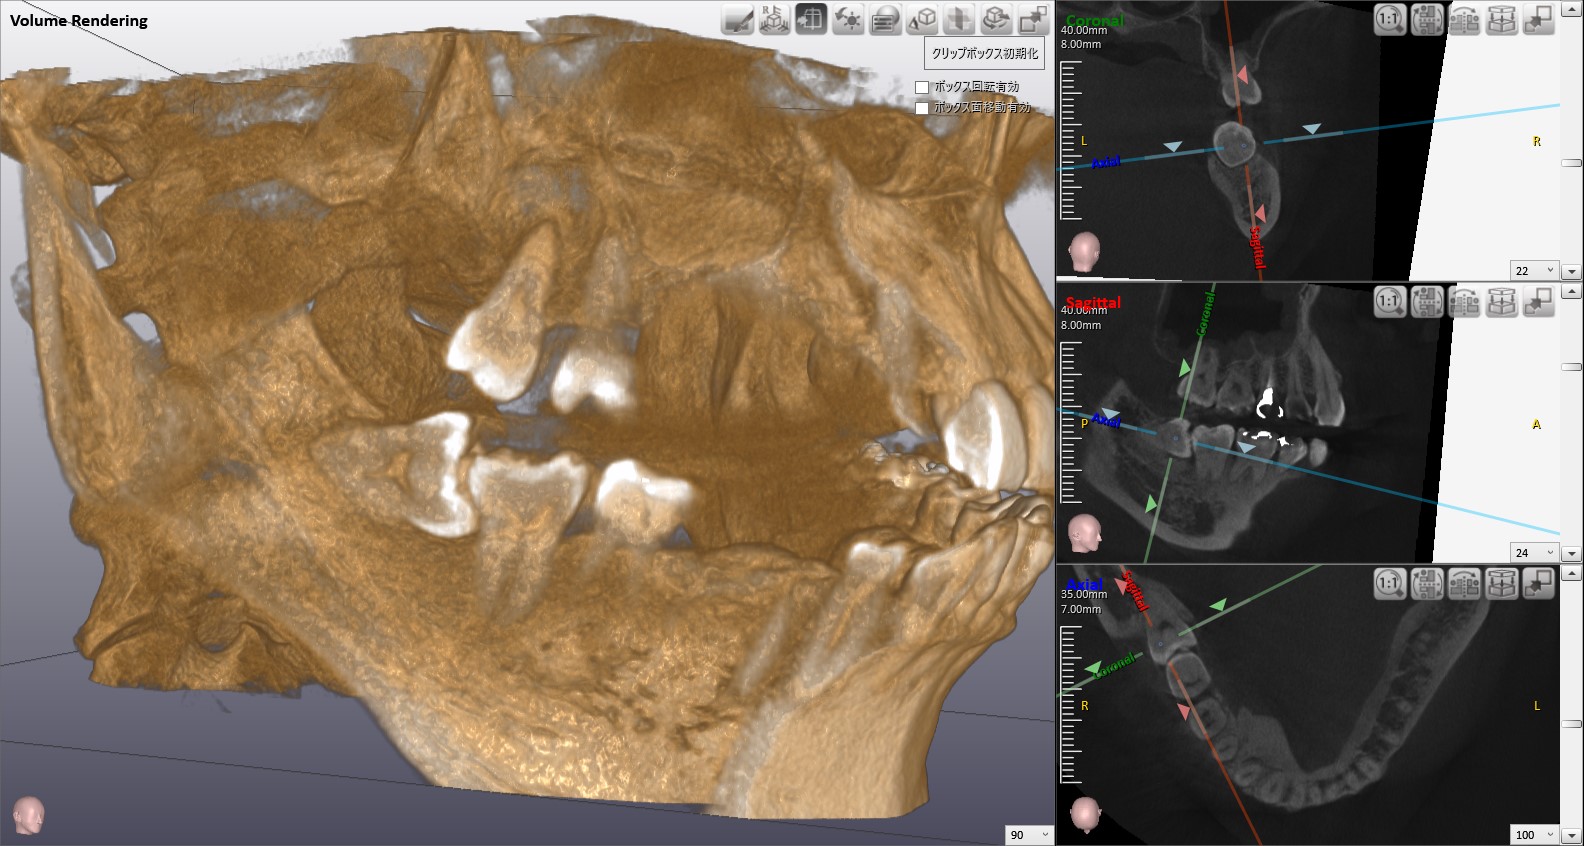

当院では、 最新鋭の歯科用CTレントゲン(NAOMI-CT) を導入しました。 従来のレントゲン画像は二次元 であったため、精度の高い顎の骨の状態を把握することができません。

CTレントゲンは、 三次元での画像が得られ、従来の平面レントゲン画像に比べ、より豊富な情報を歯科医師に提供する レントゲンシステムです。

インプラン ト治療計画での使用にとどまらず、今後の歯科診療において、 治療の安全性と確実性を向上させるため、不可欠なものと位置づけています。

患者様へ説明する際にも3D画像をご覧頂きながらの説明なので、大変分かりやすいと好評を頂いています。

歯科治療の説明というのは、患者さまにとって分かりにくいものですが、ご自身の顎の状態を理解しながら説明を受けるので、安心感も増すという声を多数頂いています。